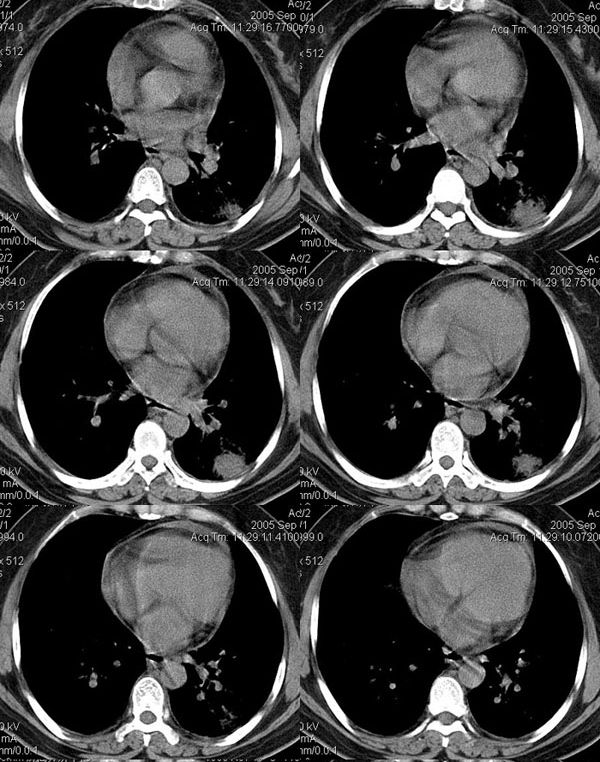

③35岁女性,因颈部包块术前检查发现右下肺圆形结节。

④男性,65岁,咳嗽、咳痰3月。

⑤男性,45岁,咳痰,痰中带血。

⑥男性,45岁。一个月前开始咳嗽。

⑦女性36y,胸痛2周住院。 手术后病理为:炎性假瘤。

⑧患者,男,48岁,于2001年因“反复声嘶9个月”在外院确诊为喉鳞状上皮癌,行手术切除。10天前患者无明显诱因出现左侧背部疼痛,进行性加重,患者无咳嗽、咳痰、发热。

实验室检查:ce125:128uml ly:0. 6x109/l wbc:10.1x109/l ne:8.3x109/l

左上肺炎性假瘤:

细支气管上皮增生、纤维母细胞增生及纤维化,间质有炎细胞浸润及淋巴滤泡形成,边缘有坏死组织。

⑨男,52岁,痰中带血两天。无明显发热,化验室检查正常。

⑩女,58岁。无不适,体检发现胸部肿物,行ct检查。

(11)女30岁,查体发现右肺上叶肿块